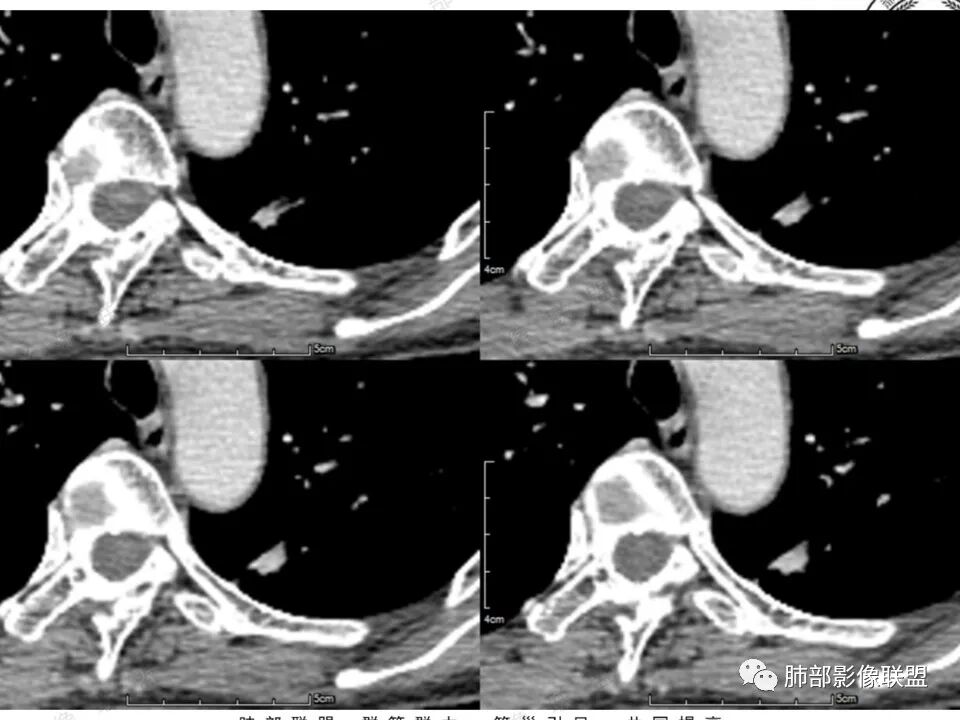

女,41岁,体检发现肺部结节。左肺上叶长形病灶,具有轻度膨胧感,刀切尖角征,胸膜粘连,早期强化见薄环强化征象,后期有延迟强化特点。病灶周围不是很干净。考虑结核肉芽肿或炎症肉芽肿。

左肺上叶尖后段实性结节,边缘有清晰磨玻璃,胸膜有牵拉凹陷,明显强化,CT值超过主动脉,考虑血管畸形(周围磨玻璃可能是出血),鉴别IAC(影像表现符合,强化不符)

患者中年女性,体检发现。胸部CT:左肺上叶后段长条形结节灶,边缘光滑,边界清楚,见分叶、毛刺、胸膜牵拉及平直征象。增强明显强化,内可见血管增粗,综合考虑恶性病变,浸润性腺癌可能大,鉴别结核。

41岁女性,左肺上叶不规则结节,边缘见似清非清的磨玻璃影,叶间裂牵拉。整体病灶边缘平直,强化明显。另左上叶外侧尚有一磨玻璃结节(蘑菇兄弟?),考虑炎性肉芽肿可能性大。强化太明显让人很纠结,会不会存在CD,但边缘又有磨玻璃影;腺癌、结核、隐球都没有见过强化这么明显的,强化程度与主动脉基本一致,不会是动静脉畸形吧。

强化太猛,血管畸形?边缘磨玻璃区,腺癌?

功能学(高强化)形态学的取舍,形态学(ggo),高强化不能除外ca

晨读反思:1.边缘磨玻璃还是比较清楚;2.有收缩力;3.强化明显提示内部有血管,说明破坏力不强。

1.中年女性,体检发现;2.左肺上叶后段长条形结节灶,边缘有膨隆,也有收缩,腺癌和炎性结节都可以,但是周围见边界清楚磨玻璃影强烈提示腺癌可能性。3.显著强化的肺结节,无论如何都应当引起我们的高度重视!尽管炎性病灶和新生物都可以,尽管强化程度不能作为诊断癌肿的依据。

4.本例结节强化程度明显低于主动脉,也缺乏血管畸形的典型的迂曲结构,血管畸形可能性不大。